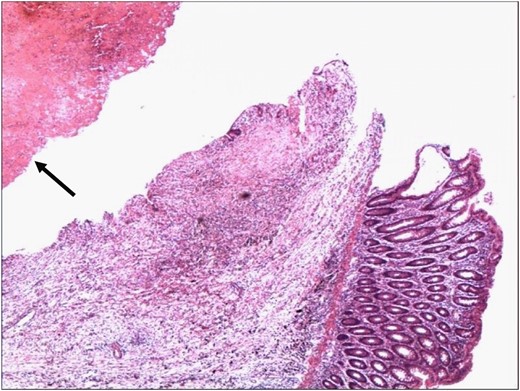

Histopathology confirmed the specimen to a SAA, with a 1 cm rupture through the colonic wall (Fig. 3A and B). On microscopic examination, the wall of the colon showed attenuation and loss of the muscle layers with bleeding into the lumen of the colon (Figs 4 and 5).

Wall of the colon showing attenuation and loss of the muscle layers. The wall of the aneurysm is indicated by the arrowhead (H&E 4×).